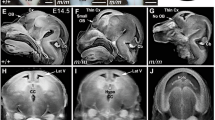

(a) Brain MRI in the proband at 5 years of age. Axial (left) and sagittal (right) T1-weighted images reveal a global reduction in the size of the cerebral structures, including the cortex and white matter, simplified gyral pattern, enlarged lateral ventricle and fully formed but diffusely thin corpus callosum. Notably, the right side is more remarkably affected than the left side. The sloping of the forehead reflects a severe decrease in the cranial-to-facial proportions. (b) Partial sequence chromatograms around codons 2595 and 3248 on exons 18 and 24, respectively, of ASPM in the patient and his parents. Red boxes denote deleted bases, and red arrows denote the start sites of heterozygous sequences due to these deletions. DNA and corresponding amino acid sequences of the wild-type and mutant ASPM alleles are also shown.

Informed consent was obtained from the parents, and molecular diagnosis was performed using genomic DNA extracted from the patient’s blood. The ethics committees of Tokushima University and Osaka Medical Center and Research Institute for Maternal and Child Health approved the study. The TruSight One Sequencing Panel (Illumina, San Diego, CA, USA) was used with an MiSeq sequencer (Illumina), followed by analysis using our pipeline for NGS data as described previously5 with a minor modification of a software update specific to the bioinformatics pipeline.6 Sequence variants with higher allele frequencies (i.e., >0.01) in the following databases were excluded to identify presumably pathogenic single nucleotide variants: 1000 Genomes Project database (http://www.1000genomes.org), National Heart, Lung, and Blood Institute Grand Opportunity (NHLBI GO) Exome Sequencing Project (ESP6500, http://evs.gs.washington.edu/EVS), Human Genetic Variation Database (http://www.genome.med.kyoto-u.ac.jp/SnpDB) and integrative Japanese Genome Variation Database (iJGVD, https://ijgvd.megabank.tohoku.ac.jp). Copy-number variation analysis using TPS data was also performed as described previously.6,7 These analyses detected two different 2- and 4-nucleotide deletions in exons 18 and 24 of the ASPM gene, namely, [NM_018136.4(ASPM_v001)], c.7782_7783del and c.9742_9745del, respectively, which caused reading frameshifts that ended with premature stop codons, p.Lys2595Serfs*6 and p.Lys3248Serfs*13, respectively. Sanger sequencing confirmed these deletions. The patient’s father and mother were heterozygous carriers of the c.7782_7783del and c.9742_9745del variants, respectively, which suggested the presence of these variations in the patient in a compound heterozygous state (Figure 1b). c.7782_7783del was present in the Human Gene Mutation Database (HGMD, Professional 2017.4, http://www.hgmd.org/) and ClinVar (http://www.ncbi.nlm.nih.gov/clinvar/) as a pathogenic variant, but c.9742_9745del was not present in any database. No other possibly pathogenic variants or gross deletions were detected in the coding regions of other MCPH-related genes in the panel for TPS (data not shown). The patient was diagnosed with MCPH5 caused by one known and one novel deletion of ASPM in a compound heterozygous state based on the results of this molecular diagnosis and re-evaluation of the affected patient’s clinical features.